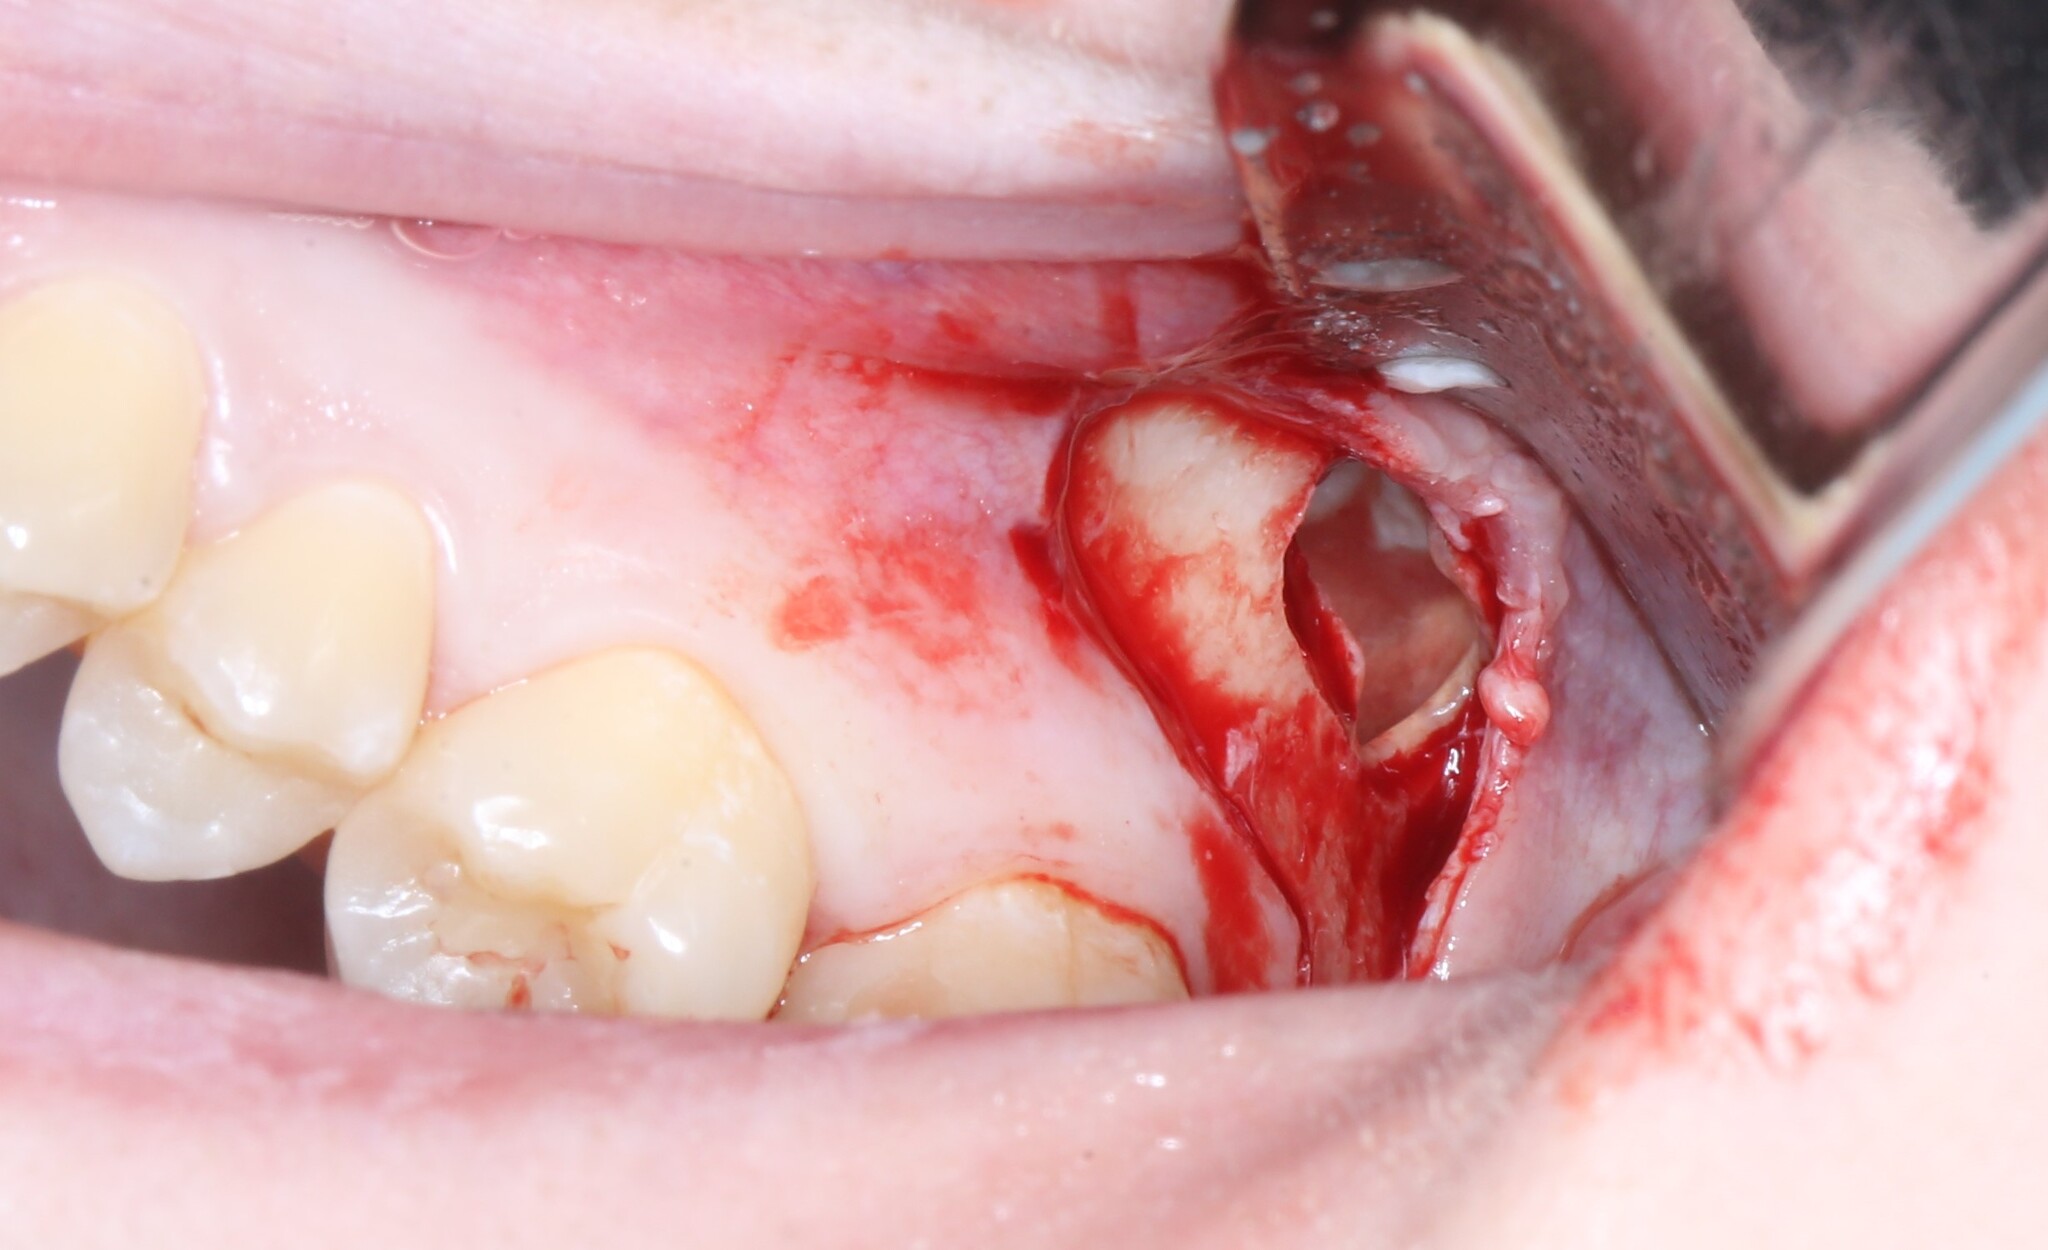

Вот и он «красавчик». Берем зажим и хватаем эту мразоту за хвост, точнее за фолликул и извлекаем:

Зуб мудрости и та самая «киста»:

Далее швы и в общем-то и все: